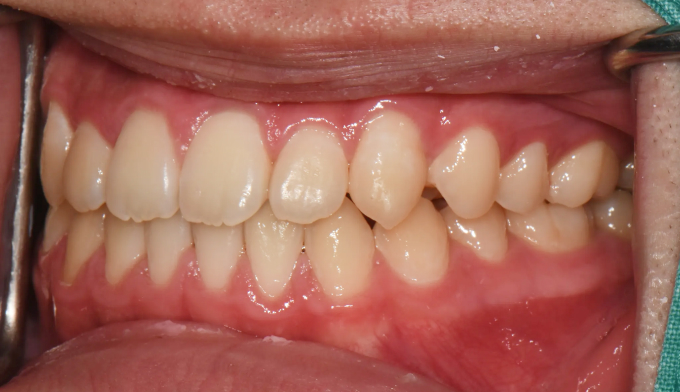

주걱턱 경향을 갖는 청소년들은 개방교합과 덧니를 동시에 갖는 경우가 많습니다. 아래턱의 과도한 성장은 혀의 위치를 아래로 처지게 만들고, 이는 위턱의 폭을 줄어들게 만들어 덧니가 생기기 쉽게 만듭니다. 그리고 과도한 아래턱의 성장은 앞니의 교합을 벌어지게 만들어 개방교합 또한 나타나게 됩니다.

그 정도에 따라 발치가 필요한 경우도 있지만, 성장기의 청소년의 경우에는 최대한 발치 없이 자연스러운 치열과 입매를 만드려고 합니다.

좁아진 위턱 악궁을 확장시켜서 치아를 배열시키고, 과도하게 앞으로 나온 앞니를 미니스크류를 이용하여 후방이동 시킵니다.

총 치료기간은 24개월 소요되었습니다.